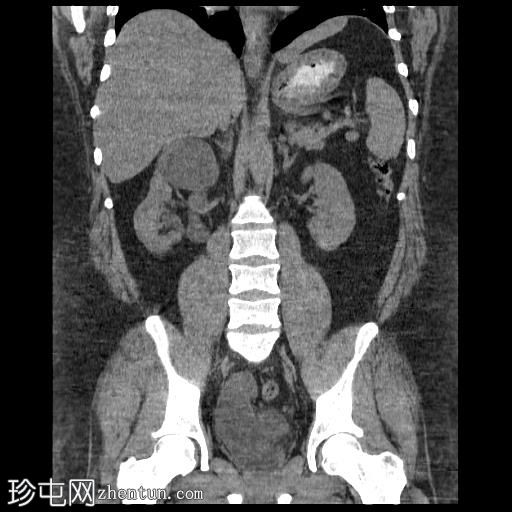

轴位肾实质期

右肾集合系统完全重复。上肾集合系统的输尿管异位开口于前列腺尿道,导致上游集合系统显著扩张。这引起肾实质的慢性改变,包括上肾组织变薄和上肾盏排尿功能障碍。

相反,右肾下肾集合系统的输尿管位置正常,无扩张或结石迹象。

左肾和输尿管外观正常。